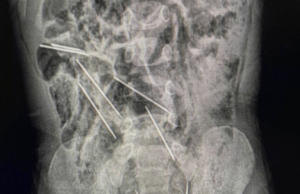

Περού: Αγόρι κατάπιε οκτώ μεγάλες βελόνες από ενέσεις για ζώα

Οι γιατροί στο βορειοανατολικό Περού έσωσαν τη ζωή ενός αγοριού 2 ετών που κατάπιε οκτώ βελόνες ενέσεων ενώ έπαιζε.

«Μόλις βρεθήκαμε στο χειρουργείο και ανοίξαμε...